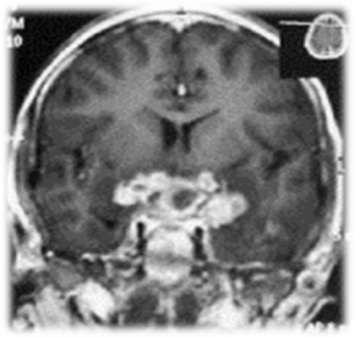

2. Рис.2. Краниофарингиома | |